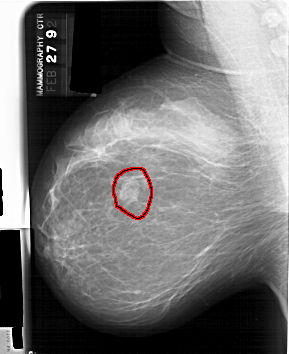

A_1389_1.LEFT_CC

LEFT_CC LINES 6046 PIXELS_PER_LINE 4681 BITS_PER_PIXEL 12 RESOLUTION 43.5 OVERLAY

FILE: A_1389_1.LEFT_CC.OVERLAY

TOTAL_ABNORMALITIES 1

ABNORMALITY 1

LESION_TYPE MASS SHAPE LOBULATED MARGINS CIRCUMSCRIBED

ASSESSMENT 4

SUBTLETY 5

PATHOLOGY BENIGN

TOTAL_OUTLINES 1

BOUNDARY